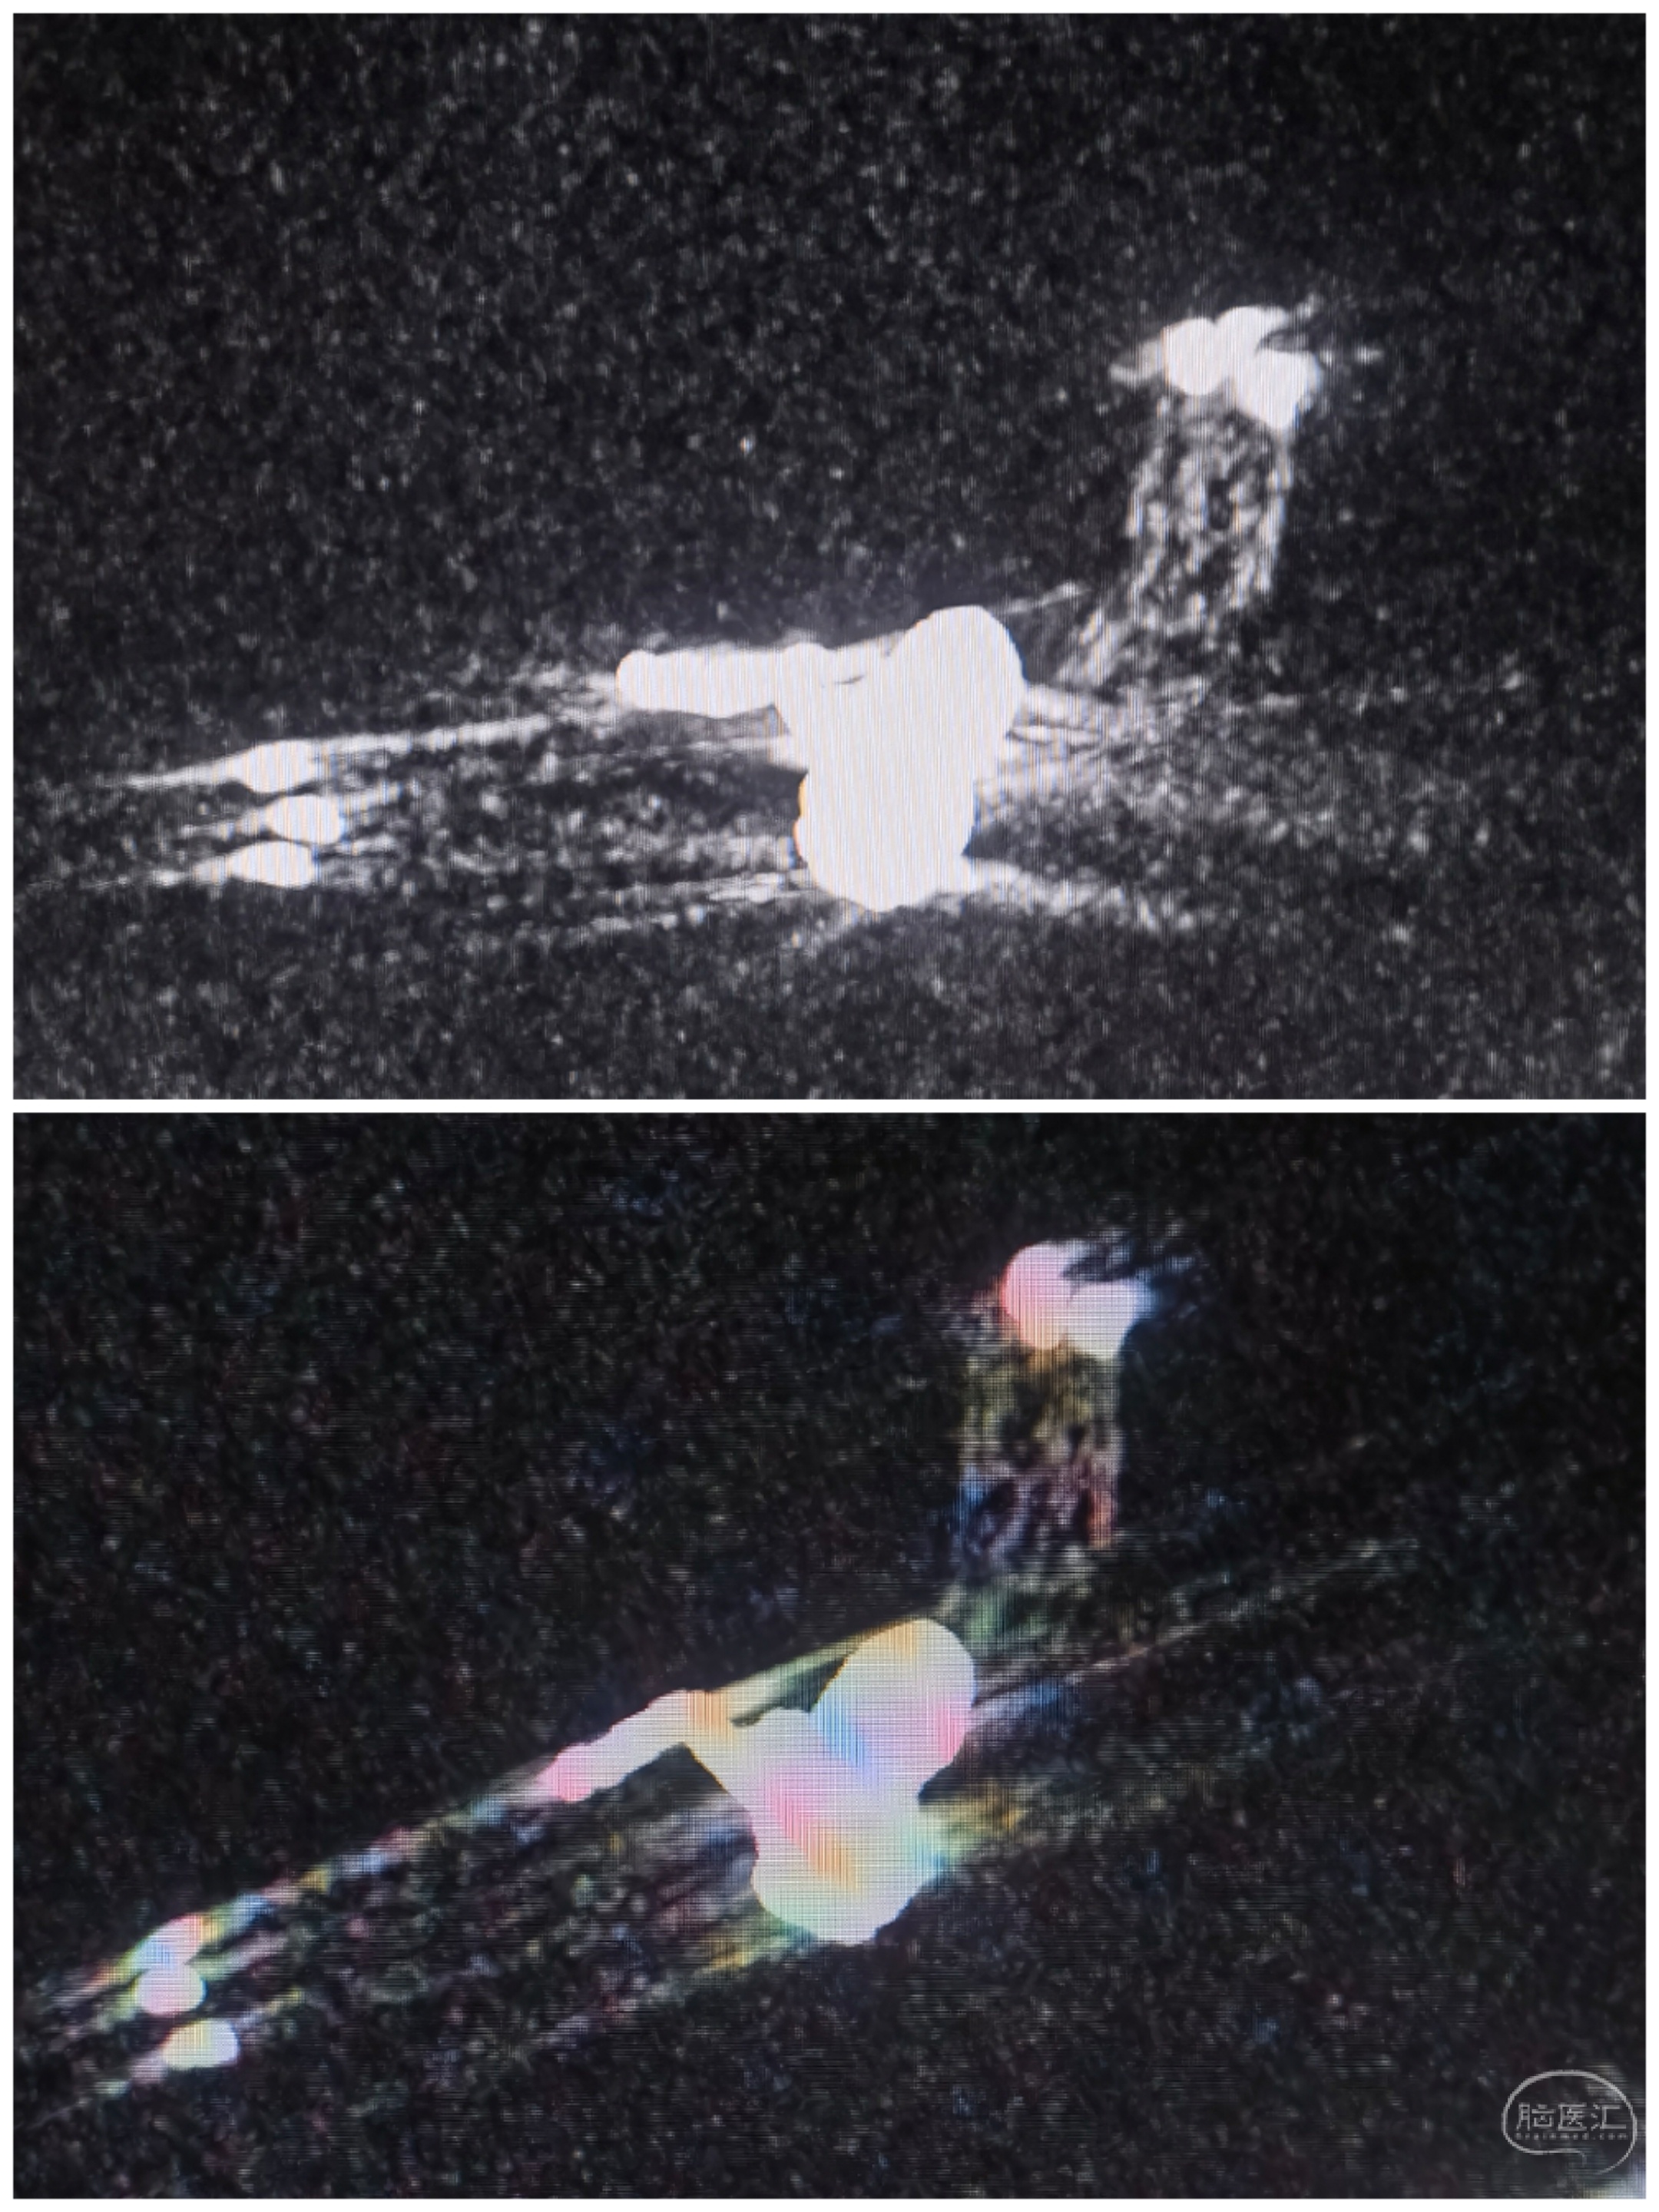

左侧颈内造影:左侧大脑前动脉优势供血,前交通动脉瘤显影

右侧颈内造影:非优势大脑前,前交通动脉瘤未见显影